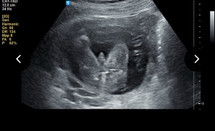

Gender girl or boy

Girl ke boy .. sono kata girl tpi mak nye xykin 😂 tkut tu bontot dia.. 21w#bantujawab #pregnancy #mohonbantujawabbunda #sharing

Kalau tak yakin boleh repeat scan. Saya pun buat detail scan masa 20 weeks. Sono kata girl tapi minta repeat masa 24 weeks. Lagi clear nampak girl.

mcm girl ni boy scan msa 20w position hmpir sama mcm baby sis 😆

mcm girl. sbb sy punya clearly blh nmpk bird kalau position mcm ni..